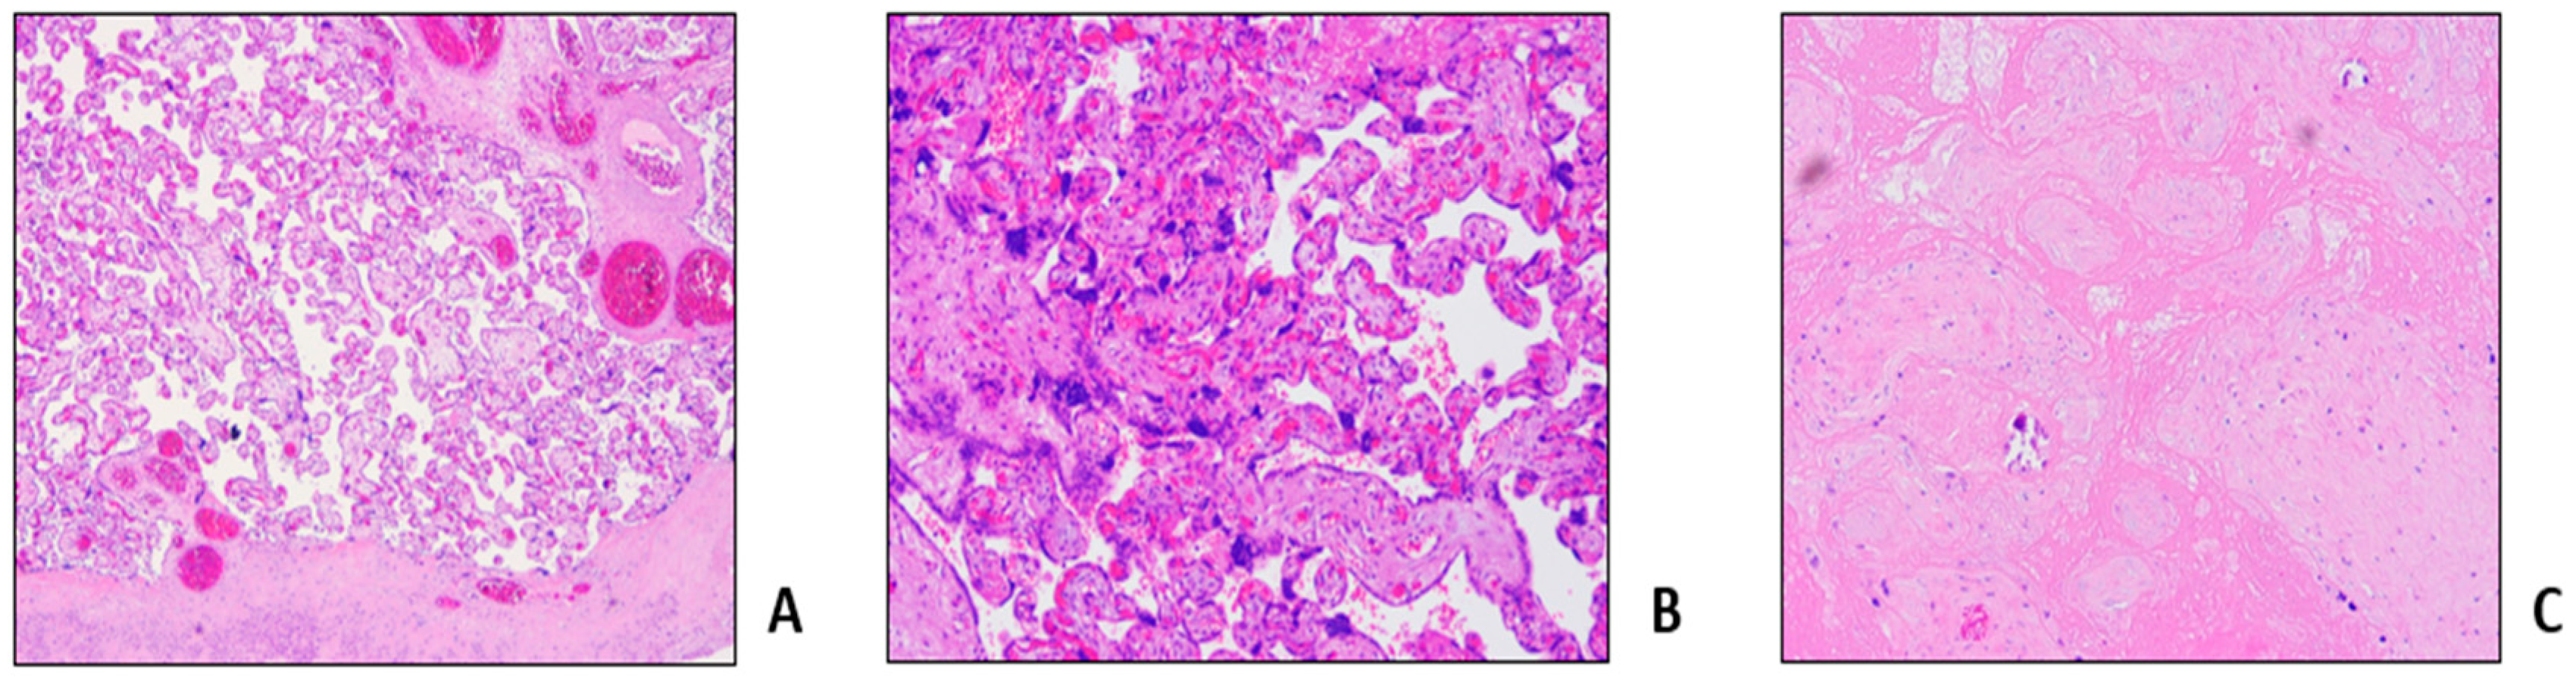

- Malinowski, A.K.; Dziegielewski, C.; Keating, S.; Parks, T.; Kingdom, J.; Shehata, N.; Rizov, E.; D'Souza, R. Placental histopathology in sickle cell disease: A descriptive and hypothesis-generating study. Placenta 2020, 95, 9–17. [Google Scholar] [CrossRef] [PubMed]